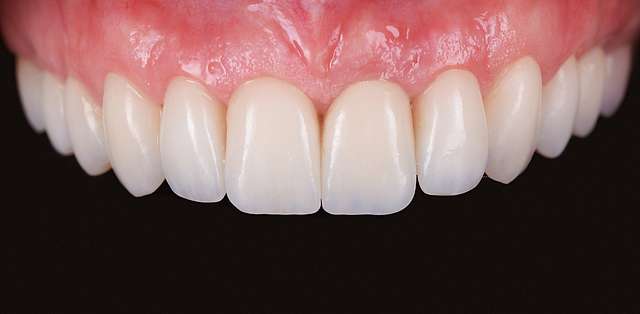

Grefa gingivala este o micro-chirurgie prin care se transplanteaza o mica bucata de tesut moale - gingie sau tesut conjuctiv (stratul intern al gingiei) pentru a acoperi un defect gingival. De obicei, acest tip de interventie este necesar pentru augmentarea implanturilor dentare, sau pentru a acoperi defecte cauzate de traume sau de afectiuni parodontale.Grefele se recolteaza din zona molarului de minte, sau de pe palat, si sunt transplantate in zona afectata.

Acesta interventie este una foarte delicata, lamele folosite pentru a efectua procedura sunt aceleasi folosite in oftalmologie, iar firele de sutura sunt si ele foarte fine. Firele se indeparteaza dupa 7-14 zile, in functie de caz, cand are loc vindecarea primara. Maturarea grefei dureaza aproximativ 90 zile, de aceea in momentul inserarii implanturilor preferam sa facem si grefa de tesut, pentru a sincroniza timpii de vindecare si ambelor proceduri.

Grefe pentru corectia defectelor gingivale

Grefe pentru corectia nivelului si a retractiei gingivale

Grefe pentru corectia culorii gingivale